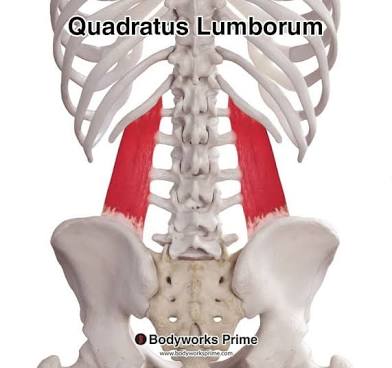

Quadratus

Square.